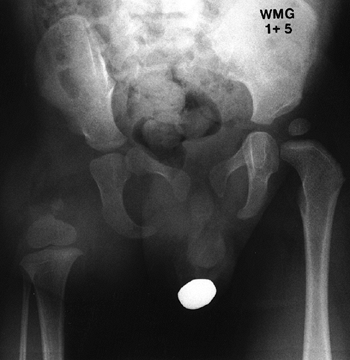

considerable varus deformity. The location of this varus deformity in

the subtrochanteric region, rather than the femoral neck, is what